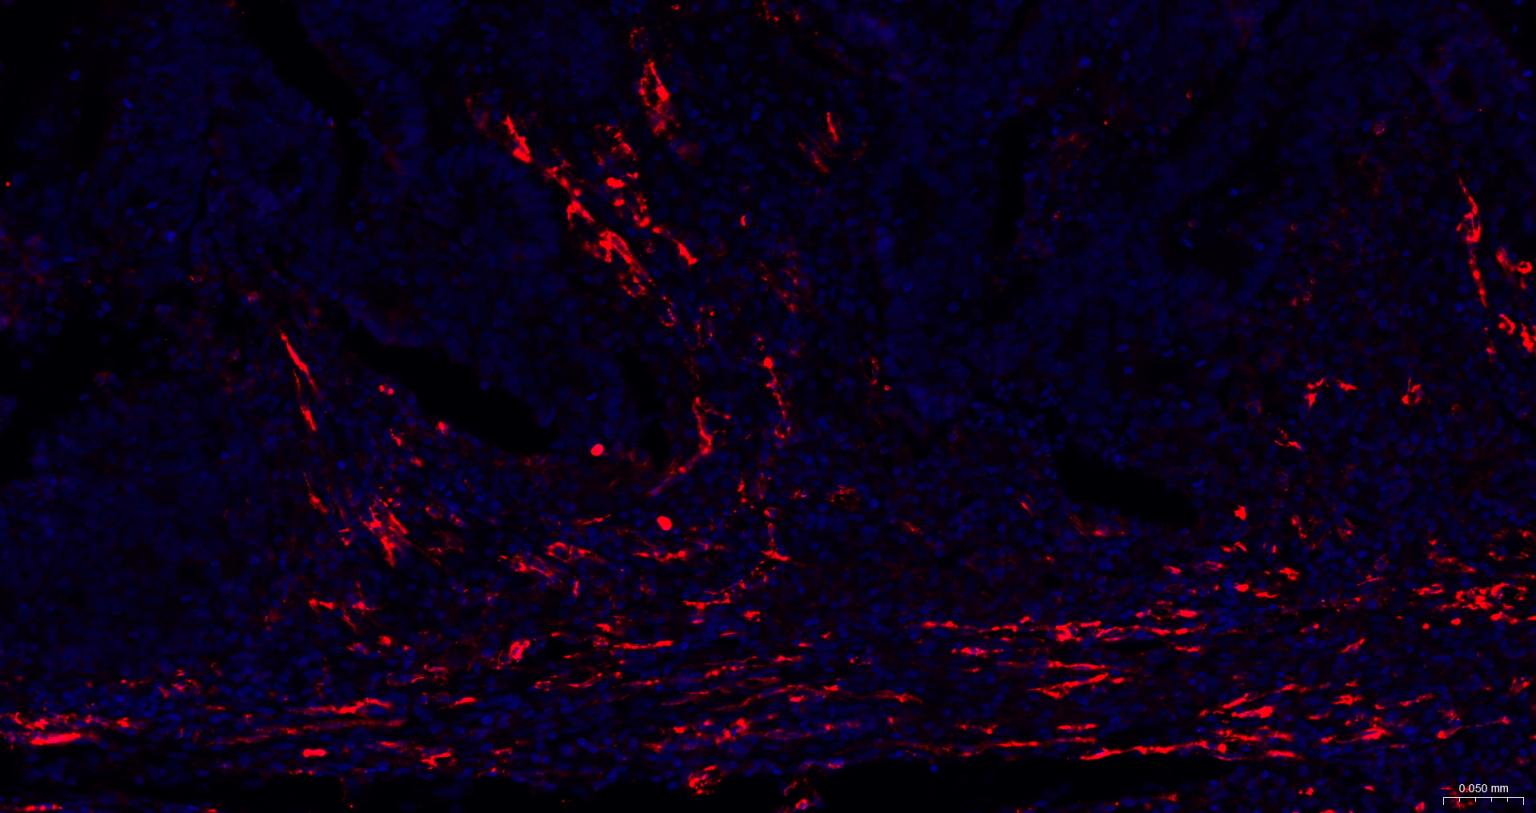

| IHC-P | Human | 1:200-2000 | |

Expressed on platelets and leukocytes and is primarily concentrated at the borders between endothelial cells (PubMed:18388311, PubMed:21464369).

Cell adhesion molecule which is required for leukocyte transendothelial migration (TEM) under most inflammatory conditions (PubMed:19342684, PubMed:17580308).